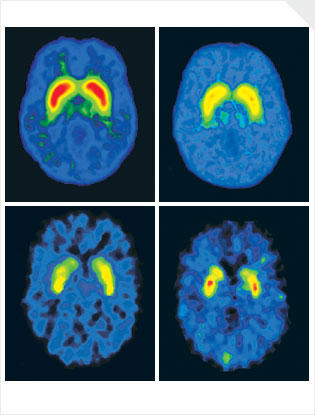

The study was done by Valerie Voon, a lead researcher at Cambridge University. Twenty young men between the ages of 19 and 34, whose lives were controlled by porn, agreed to have their brains scanned while they viewed explicit pornographic images. A control group of men who did not use porn compulsively were shown the same images. The scans were done to see how their reward centers reacted. When the data was analyzed, the results were “astounding.” The reward centers of the compulsive users were twice as active as those in the control group; similar to the responses of drug and alcohol users.